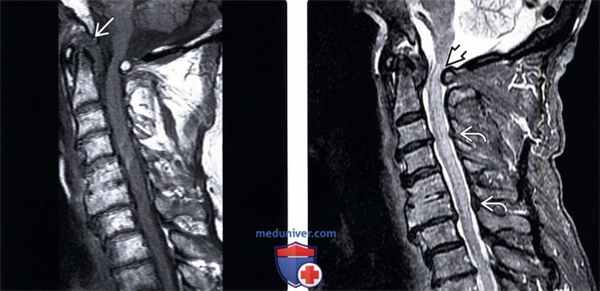

(Слева) Т1-ВИ, сагиттальная проекция: низкоинтенсивная псевдо-опухоль, расположенная позади зубовидного отростка и вызывающая сдавление вентрального листка твердой мозговой оболочки и спинного мозга. Также здесь отмечается и задняя компрессия спинного мозга за счет смещенной кпереди задней дуги атланта.

(Справа) На STIR МР-И видны признаки пирофосфатной артропатии атлантоаксиального сочленения с формированием псевдо -паннуса, сдавливающего спинной мозг, и миеломаляции на фоне переднего подвывиха С1. Обратите внимание на признаки кальцификации желтой связки, ставшей в данной случае дополнительной находкой.